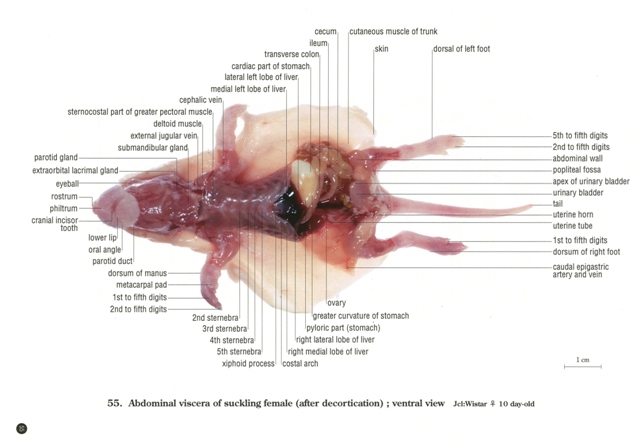

お得な情報満載 ラットの断面解剖アトラス 出版事業 - 医学一般